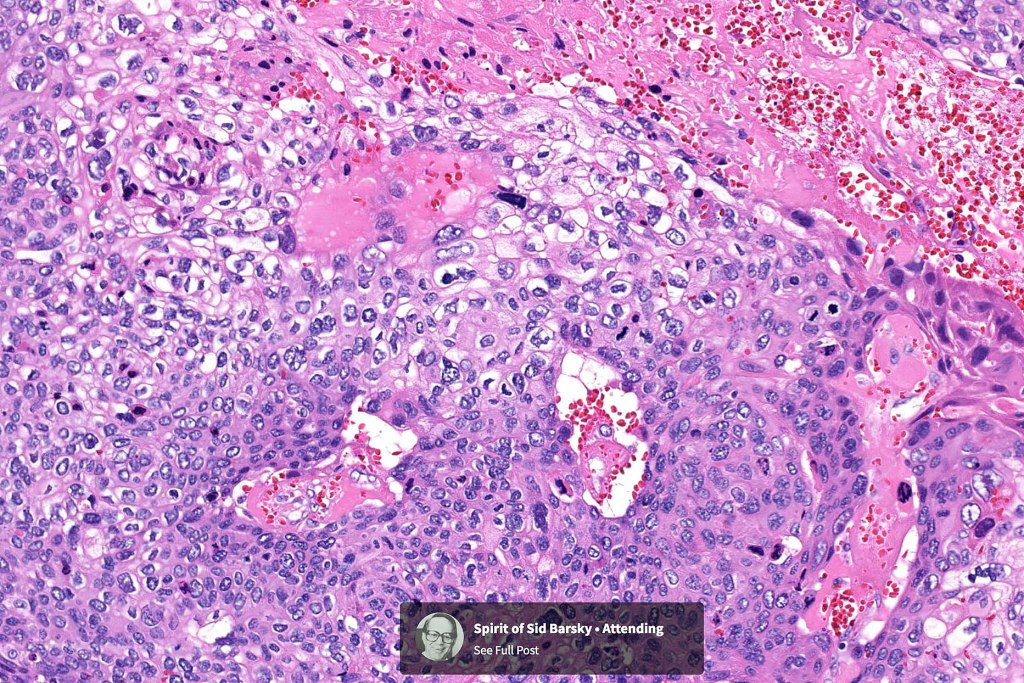

Histological features

•Nuclear pleomorphism and nuclear hyperchromatism

•Marked mitotic activity

•Abnormal mitoses

•Necrosis